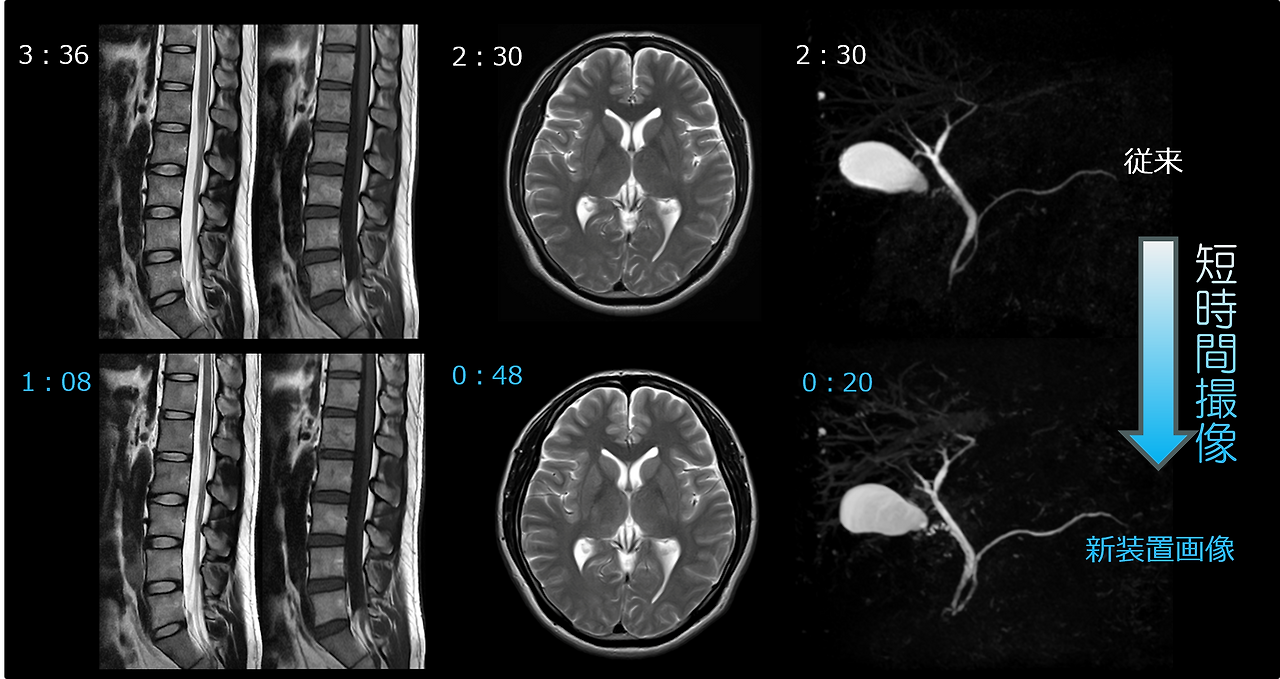

또한, MRI 장비의 성능(1.5T, 3.0T)에 따라서도 비용이 다를 수 있습니다. 3.0T 고해상도 MRI는 영상 품질이 우수하지만 검사비가 10~20%가량 더 비쌉니다.

뇌 MRI 검사 시간과 절차

뇌 MRI는 일반적으로 30~50분 정도의 시간이 소요됩니다. 하지만 검사 내용에 따라, 특히 조영제를 사용하는 경우에는 1시간 이상이 걸릴 수도 있습니다.